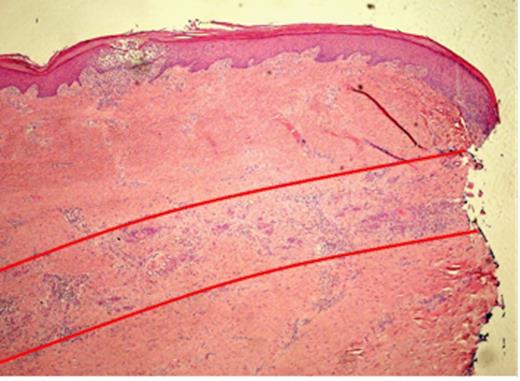

Plantar view of the left forefoot showing a large keratinising Squamous Cell Carcinoma over the medial aspect of the forefoot extending to the plantar aspect of the great toe, accompanied by extensive superficial invasion of the subcutis, extending 15mm radially from area of ulceration (red line)

Pathological examination of the plantar fascia revealed extensive invasion of the subcutis, extending radially for up to 15mm beyond the area of ulceration (Fig. 1). The tumour was 6mm thick and confined to the subcutaneous plane, well clear of the underlying muscle and bone. Microscopic examination of indurated areas revealed a moderately differentiated SCC invading the deep dermis in a band-like fashion parallel to the epidermis without evidence of peri-neural or deep structure involvement (Fig. 3).